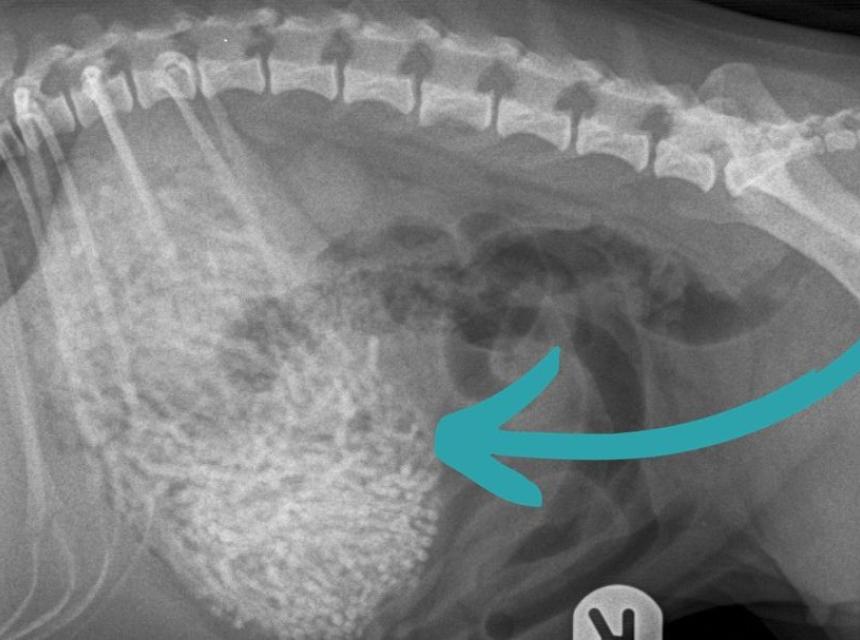

Prvi pregled u veterinarskoj ordinaciji pokazao je da pas ima nešto neobično u stomaku, pa su se odmah odlučili na operaciju.

Veterinarka Emili Vitbi (Emily Whitby) rekla je da su uklonili 50 do 60 gumica teških 200 grama – Ham je teška samo šest kilograma.